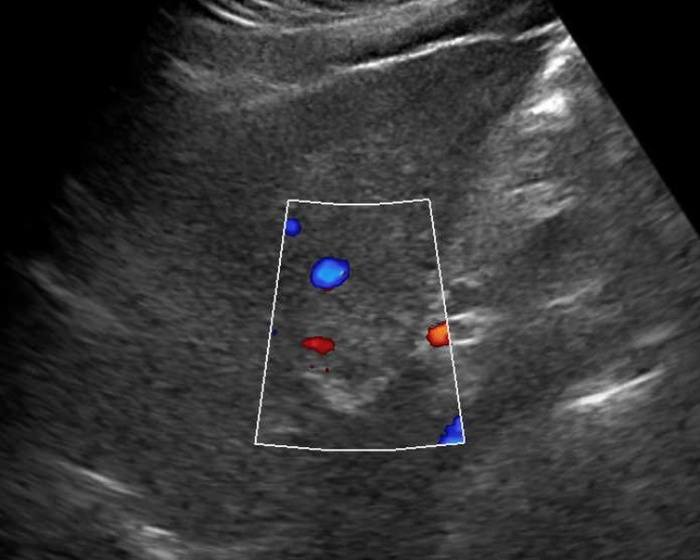

Ung thư đường mật

» Thông tin: Nữ giới – 56 tuổi.

» Lâm sàng: Viêm gan C.